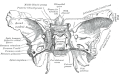

Appendix Gray1073.png

Lisa

21:47, 24 February 2018

500 × 405; 46 KB